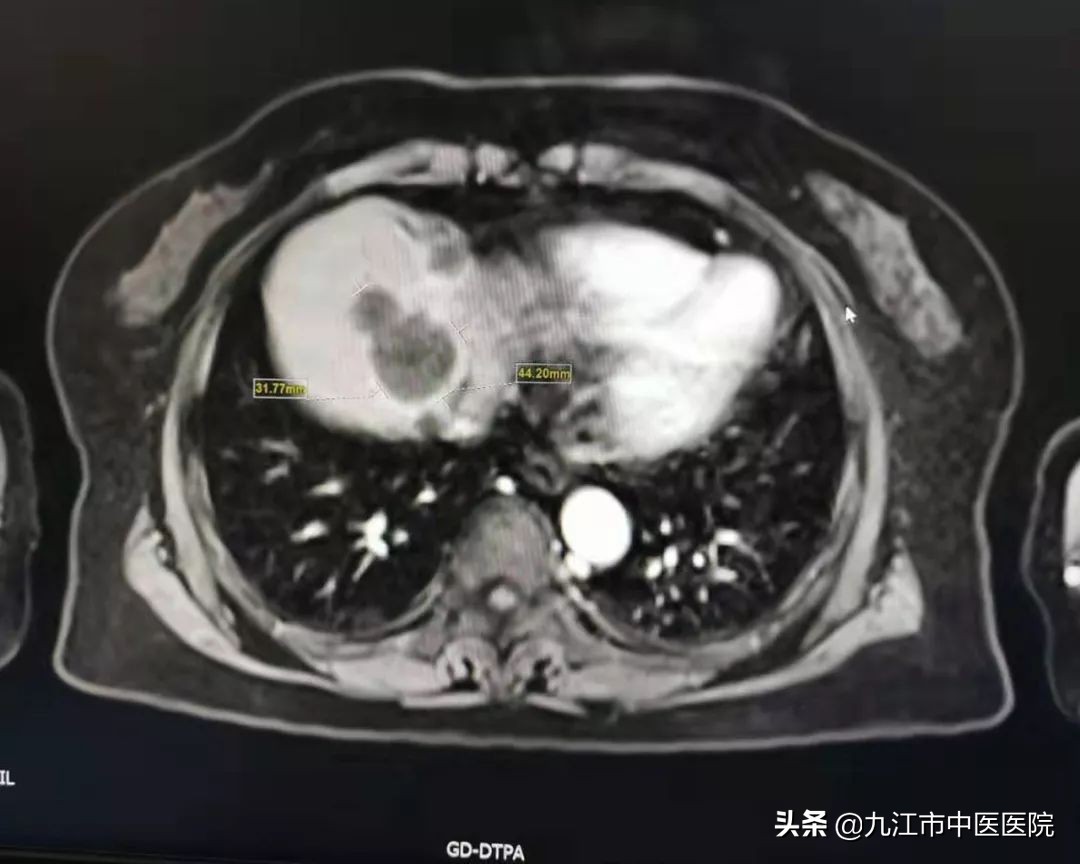

据经管医生何刘鑫介绍,该病友为一名60多岁女性,19年因上腹部胀痛不适来到九江市中医医院就诊,科主任汪波接诊后,结合CT、磁共振等相关检查确诊为胰腺恶性肿瘤伴有肝脏多发转移。

在经过9个月的精心治疗,该病友胰腺内肿块基本消失,肝脏最大占位也从29mm缩小至6mm,肿瘤标志物CA199从3万多降至正常范围,患者现无明显不适。

胰腺治疗前